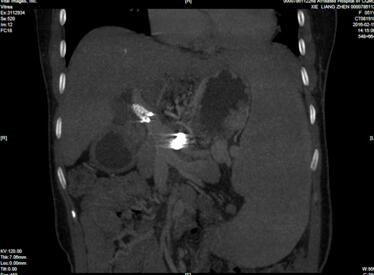

我科另一患者谢女士因自身免疫肝硬化、脾大、脾功能亢进病魔缠身4余年,多次于外院发生上消化道大出血,反复呕血、黑便多次,经全科讨论决定在2016-2-24日,由刘作金主任医师主刀对其行联合脾动脉介入栓塞术+腹腔镜下巨脾切除术微创治疗,手术顺利完成。此次手术是我院第一次联合介入放射及腹腔镜下脾切除术,这标志我院腹腔镜下脾切除微创治疗术及联合放射介入、超声介入等微创治疗,又上一个新台阶。

据刘作金教授介绍,手术中我们最担心的就是大出血,全腹腔镜下巨脾切除术一大特点是:我们采取了精细解剖脾门,逐一处理脾蒂血管后分离脾周的方法,有效的防止了大出血,从而保障手术的安全进行。术后两日两位患者恢复情况良好,能下床行走,自行进食流质饮食,不日即可出院。